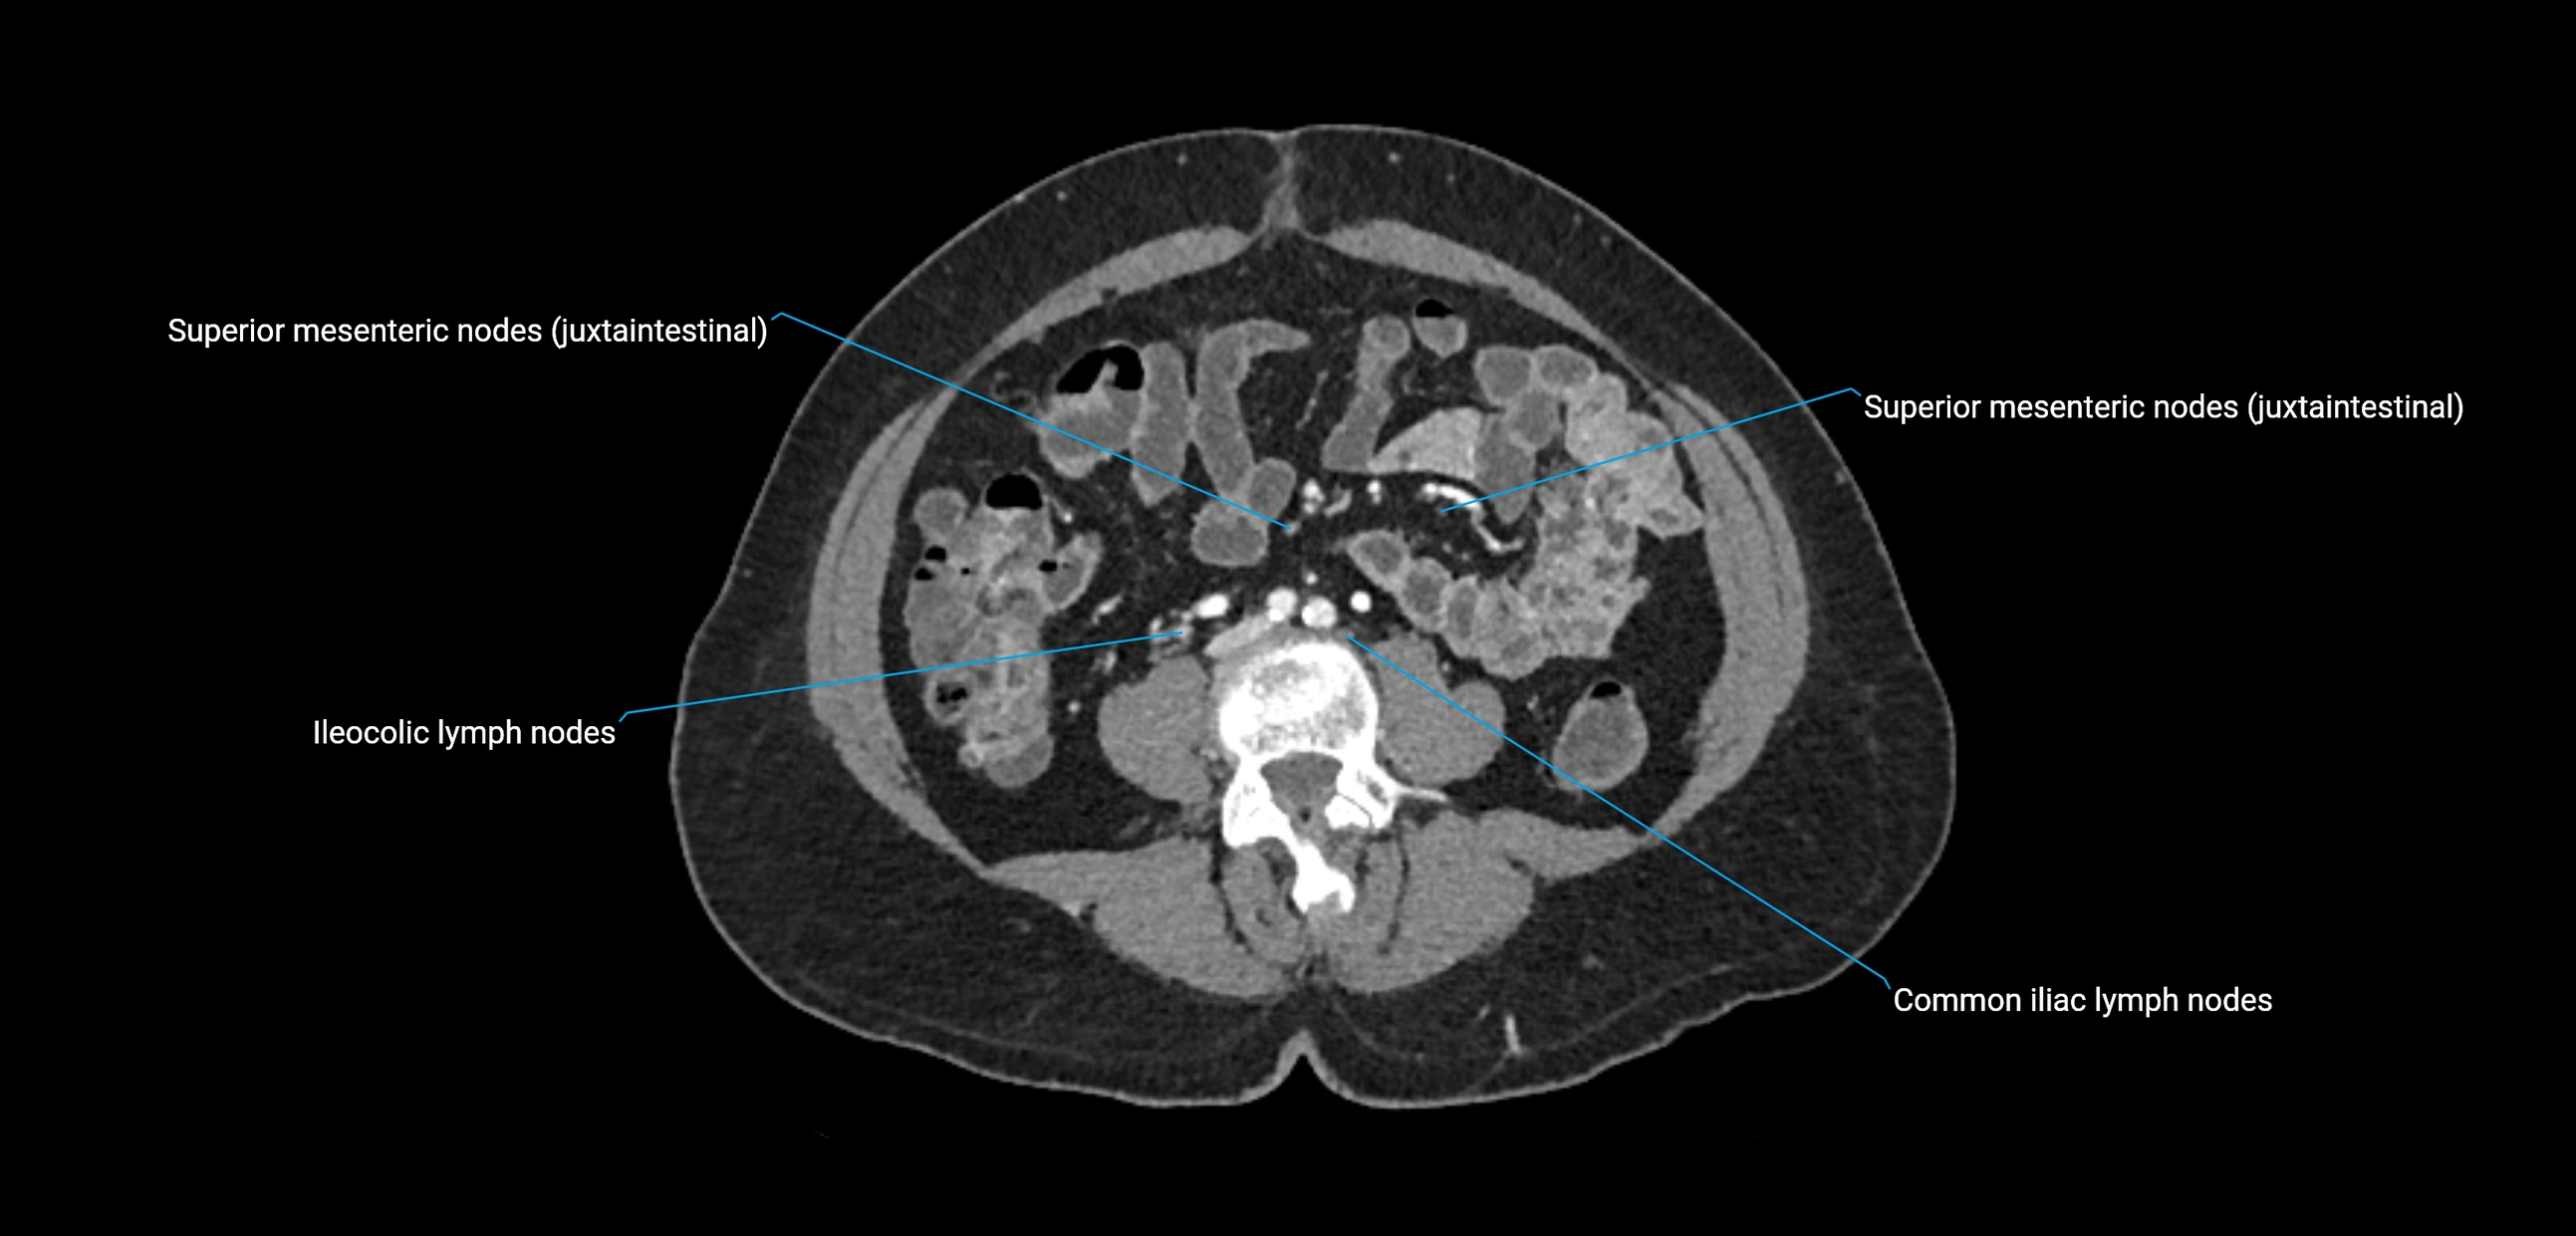

CT Appearance

CT Pre-Contrast:

• Nodes appear as soft-tissue density nodules adjacent to the aorta and IVC

• Calcification may be seen in chronic infections (e.g., tuberculosis)

CT Post-Contrast:

• Normal nodes enhance homogeneously

• Malignant nodes may show heterogeneous enhancement, central necrosis, or conglomerate formation

• Size >1 cm short axis is suspicious, though morphology and distribution are equally important